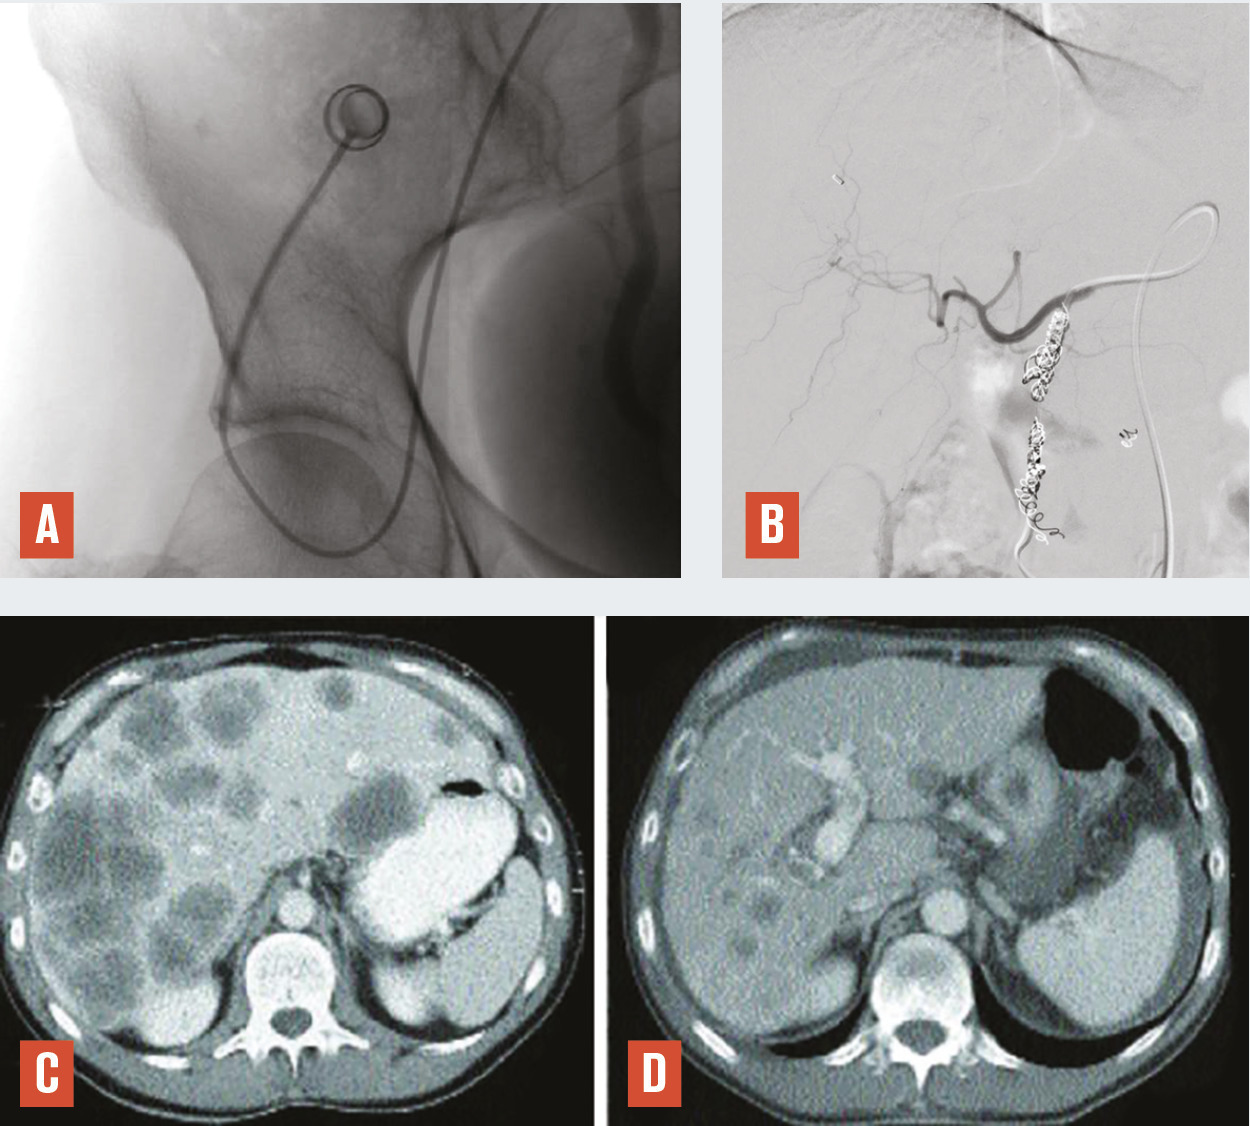

La radiologie interventionnelle a commencé à se développer grâce au progrès de la navigation intra- artérielle à l’aide de cathéters de plus en plus miniaturisés.3 Le positionnement de l’extrémité du cathéter dans l’artère hépatique, voire dans une de ses branches segmentaires à partir d’une voie d’abord périphérique le plus souvent fémorale, permet une obstruction (embolisation)4 [fig. 1 à 4 ], une libération locale intra-artérielle de chimiothérapie5 et plus récemment de microsphères chargées de médicaments6 ou de particules radioactives permettant une irradiation interne sélective du foie.7, 8 Le but est d’obtenir une concentration élevée des agents cytotoxiques au plus près des tumeurs dans le foie avec un faible relargage dans la circulation générale. Enfin, il est possible de placer par radiologie interventionnelle un cathéther dans l’artère hépatique relié à une cham-bre implantable (fig. 5 ). La chimiothérapie est ainsi injectée directement dans le système artériel du foie de façon répétée (en général toutes les deux semaines) avec des concen- trations intrahépatiques de médi- caments bien supérieures à celles obtenues après une injection par voie veineuse. L’objectif est d’obtenir une réduction tumorale qui permette au patient d’être éligible à une éventuelle chirurgie curative.9

Méthodes locorégionales par cathétérisme artériel

Il s’agit de l’injection locale dans le foie de médicaments, d’agent d’embolisation ou d’agents radioactifs. Après cathétérisme artériel à partir le plus souvent de l’artère fémorale et repérage des lésions, le radiologue interventionnel injecte localement différents types d’agents selon le type de métastases, l’extension de la maladie et les traitements antérieurs, après décision en réunion de concertation multidisciplinaire (fig. 1 à 4 ).

Il existe aussi la possibilité de réaliser une chimiothérapie intra-artérielle répétée sur plusieurs cycles par la mise en place d’un cathéter dans l’artère hépatique branchée sur une chambre implantable placée dans la région inguinale (fig. 5 ).

Ces traitements sont réalisés sous anesthésie locale, sauf pour la mise en place d’un cathéter avec chambre implantable, qui se pose sous anesthésie générale. La prise en charge ambulatoire est possible.